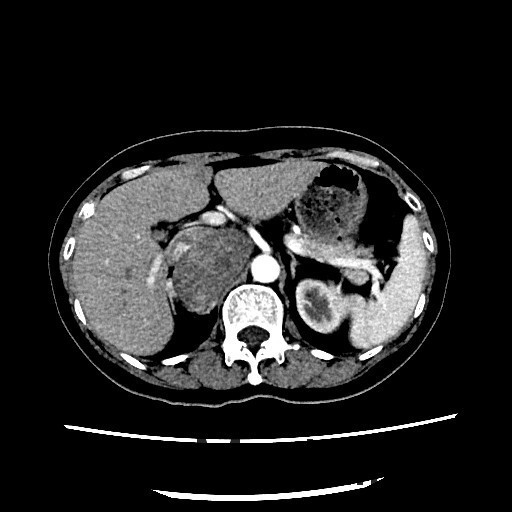

查体:血压:152/80mmHg。双肾区无红肿、隆起,双肾区叩击痛(-),双侧肋脊点、肋腰点压痛(-)。 辅查:CT平扫+增强扫描示:右侧膈下肾上腺区和左侧腰大肌病灶, 考虑为良性肿瘤,嗜铬细胞瘤可能性大,未除外其他

随访:病理回报示:嗜铬细胞瘤。 讨论:该例嗜铬细胞瘤具有较典型的影像表现,我们能看到右侧肾上腺椭圆形肿块,边界清楚,直径较大,这可区别于肾上腺腺瘤,后者一般小于2cm。增强扫描肿块明显强化,并可见无强化低密度区,可能是肿瘤常坏死或陈旧性出血引起。而且该患者有嗜铬细胞瘤引起的继发性高血压,不过追问病史没有典型的阵发性高血压发作。